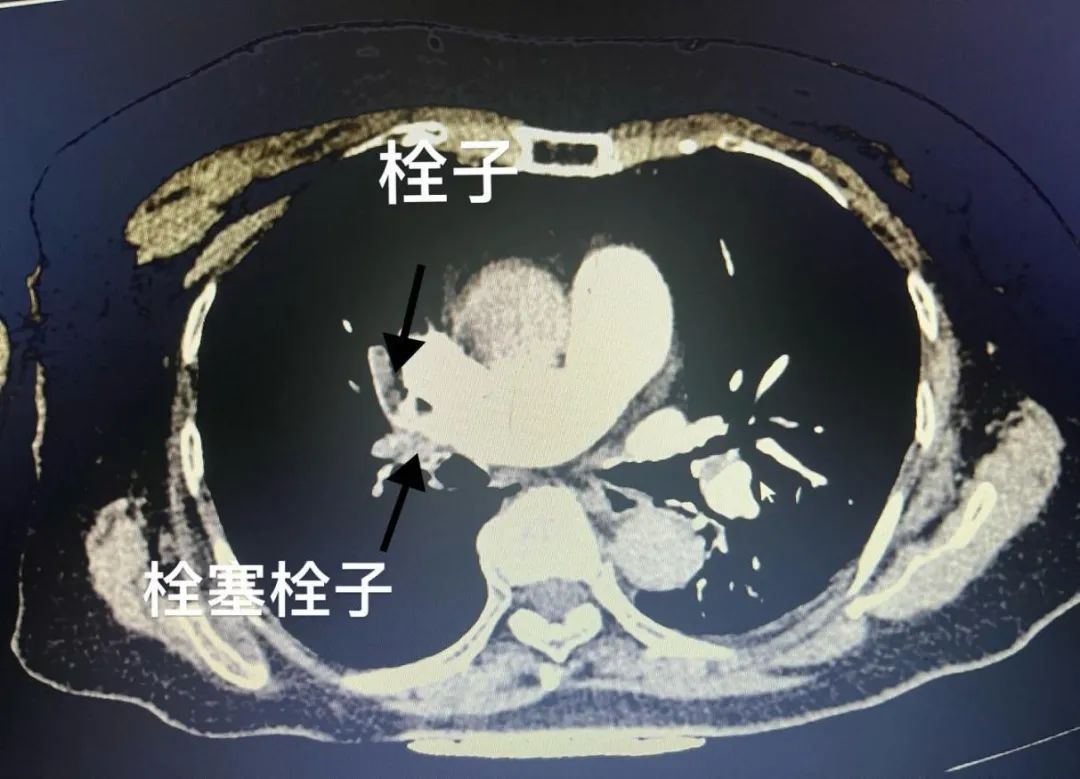

近日,74岁的何婆婆在平路慢行时出现呼吸困难,胸闷、心悸等症状,剑突下伴压榨感,于是到合江县人民医院急诊医学科就诊。医生考虑为急性肺动脉栓塞,在询问病史、完善相关检查后证实该诊断。

医生向患者家属沟通该疾病的潜在风险及治疗方案后,患者家属立即选择行下腔静脉滤器置入+肺动脉栓塞取栓溶栓术。 术后继续行标准抗凝治疗,抗凝5天后复查CTPT。 经过血管外科医护的精心治疗,何婆婆顺利出院了,术后继续抗凝3-6月,门诊随访既可。

要确诊肺栓塞,我们需要结合患者的症状,体征和一系列辅助检查。其中,CT肺动脉造影是目前诊断的金标准,如果可以看到动脉分支栓塞,那么就可以诊断为肺栓塞。此外,化验D-二聚体、凝血功能,以及心电图、彩超等也可以作为辅助诊断手段。